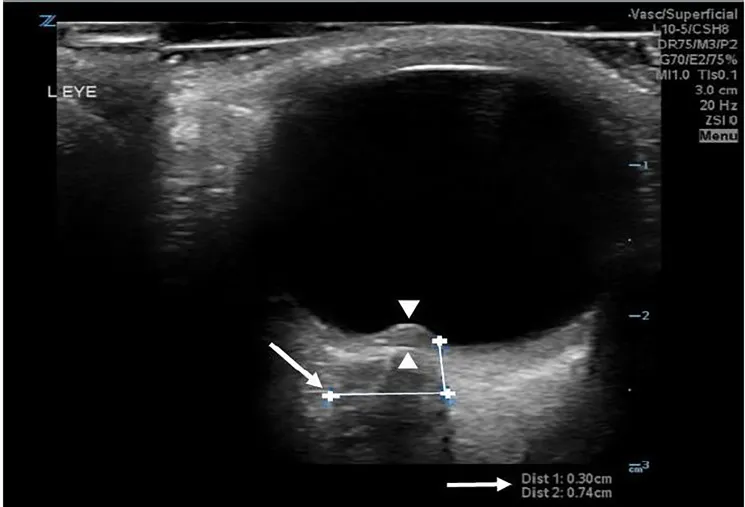

ONSD를 측정하기 위해서는 3×5를 기억해야 한다.

양쪽 눈에서 Globe의 posterior aspect에서 3mm 뒤쪽에서 측정한다

5 mm 미만은 정상, 5~6 mm 는 indeterminate, 6mm 초과는 증가한 것으로 판단

optic disc의 ant. peak 와 globe의 post. surface 사이 거리 > 0.6 mm

→ Papilledema